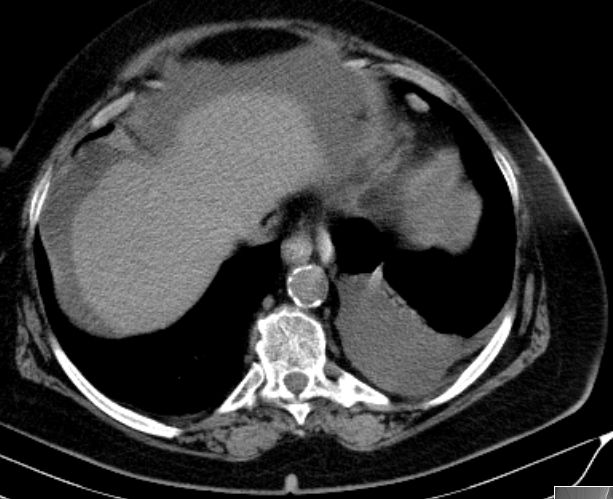

73-jährige Frau mit Ascites, Pleuraerguss links und Unterbauchtumor.  Das Netz ist komplett in einen Omental-Cake umgewandelt. An der Zwerchfellkuppe miliare Tumoraussaat.

Beide Adnexe in knapp kindskopfgroße blumenkohlartige Tumoren umgewandelt.

Im Douglas finden sich pararektal mehrere bis zu pflaumengroße Tumorknoten.